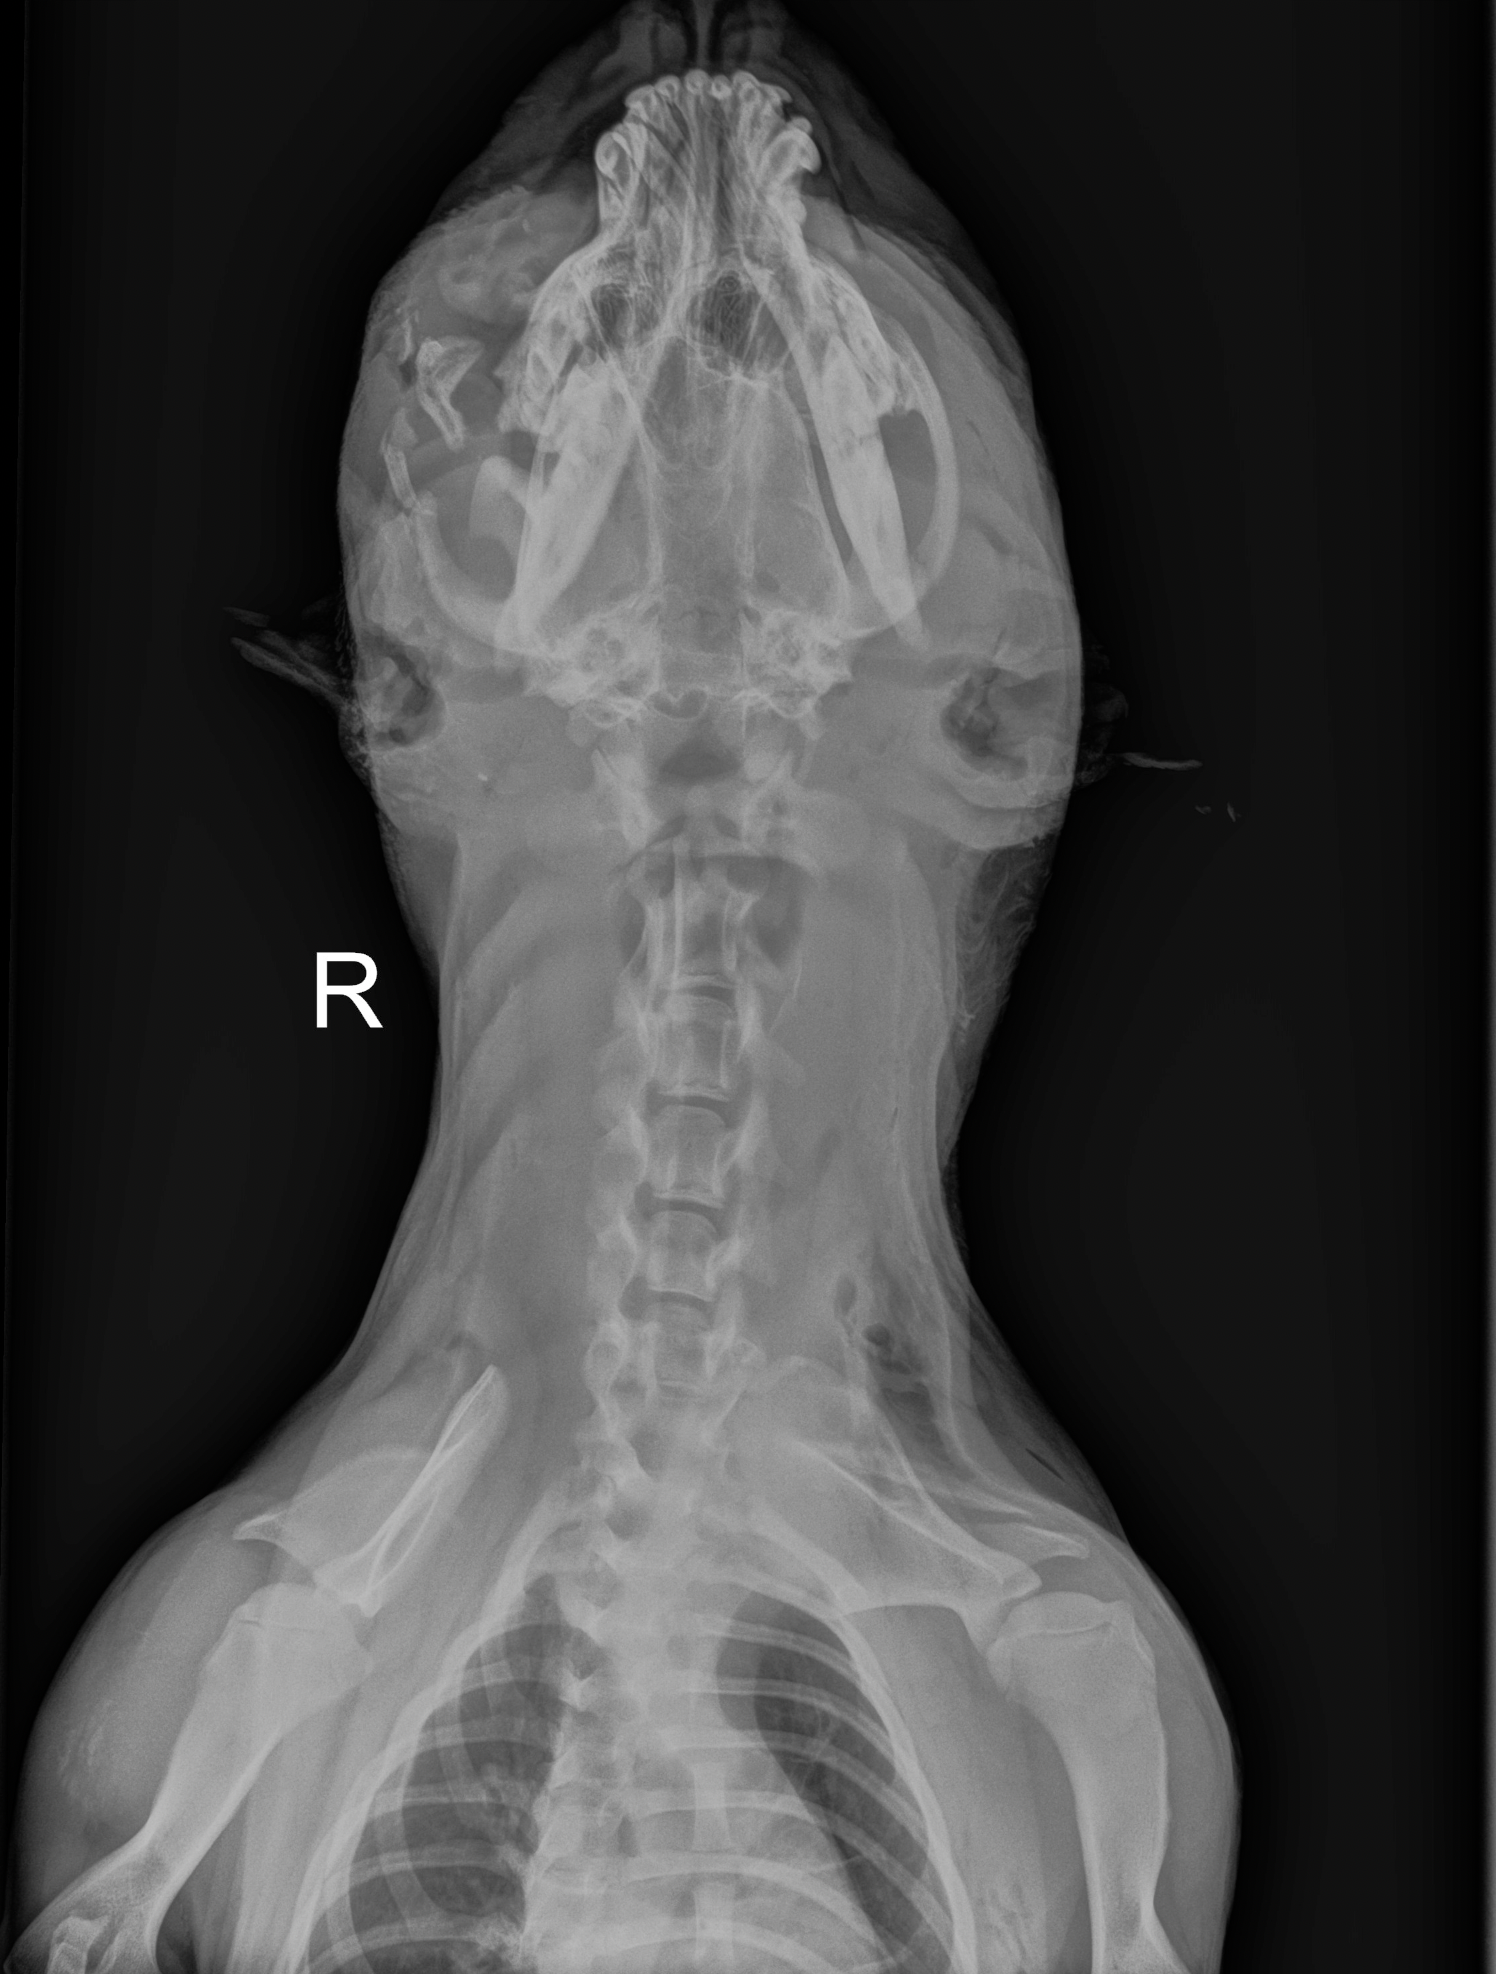

Once Jessie was stabilized and sedated, her wounds were carefully cleaned. That’s when the full truth emerged—revealed by X-rays that told a story her body had been silently holding.

The damage was severe. The bone beneath her eye—the orbital bone—was completely shattered. Several teeth on the same side were broken down to their roots. While the worst injuries were concentrated on one side of her face, hidden wounds were also discovered behind her ears and across the top of her head.

What baffled the medical team was what wasn’t there. No bullet fragments. No injuries to her legs or torso. Whatever caused this trauma seemed focused solely on her head, deliberate and brutal.